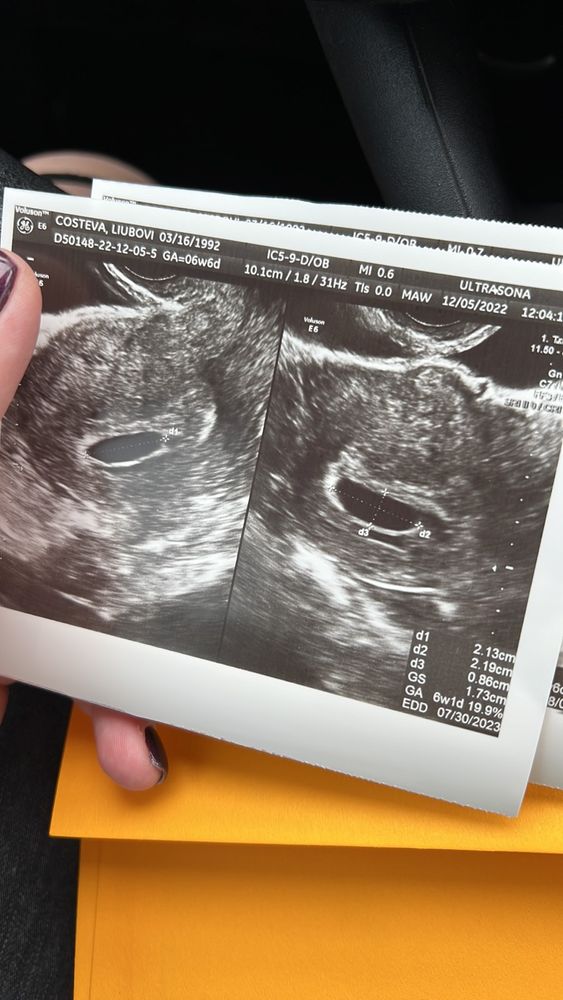

Перенос эмбриона. Нет сердцебиения.

Скорее всего у вас анембриония, на таком сроке правда уже было бы видно и эмбрион и сердечко У меня в 6+4 уже было сердечко

Наверное очень печально но это анембриония. К 6 неделям уже сб+ ... Пересдайте контрольное узи...

Tatyana, спасибо. Еще сделаю узи. Но на таком сроке как у меня должно биться сердце и очень хорошо биться. Поэтому я мало верю в положительный исход